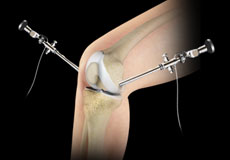

Knee Arthroscopy

Knee arthroscopy is a common surgical procedure performed using an arthroscope, a viewing instrument, to diagnose or treat a knee problem.